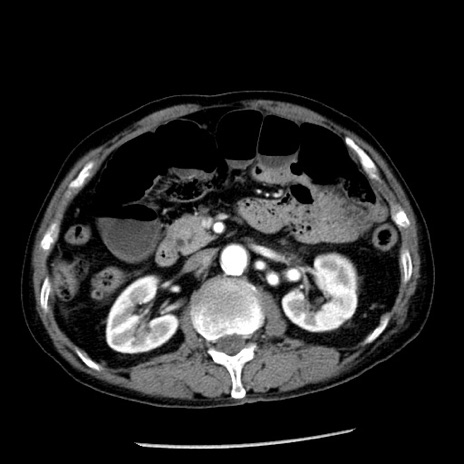

症例26(横断像)

【症例】80歳代男性

【主訴】嘔吐

【現病歴】昨晩2回嘔吐あり、今朝になっても嘔吐あり。来院。

【既往歴】胃潰瘍

【身体所見】意識清明、BT 37.6℃、BP 166/95mmHg、HR 100bpm、SpO2 97%、腹部:平坦・軟、腸蠕動音聴取良好、圧痛なし。

【データ】WBC 21900、CRP 1.46